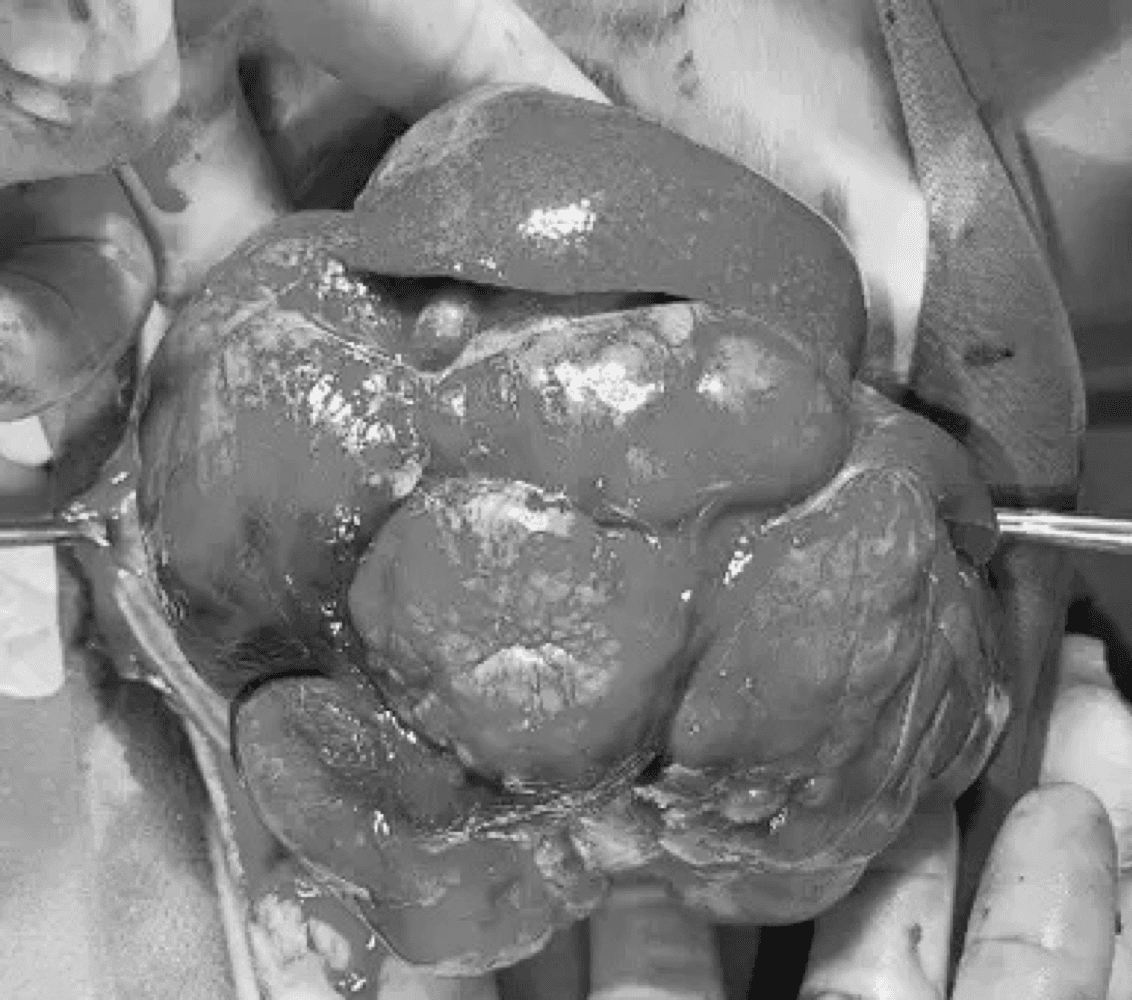

간, 담도 수술은 수술뿐만 아니라, 수술 후 중환자 관리도 중요하기 때문에 외과와 내과의 협진이 매우 중요합니다. 동탄시티동물의료센터에서는 최신 수술 장비의 도입으로 간담도 수술에서 출혈 및 부작용을 최소화 하였으며, 수술 후 협진 시스템을 통해 수술 후 관리에도 최선을 다하고 있습니다.

간종양

담석

담낭점액종